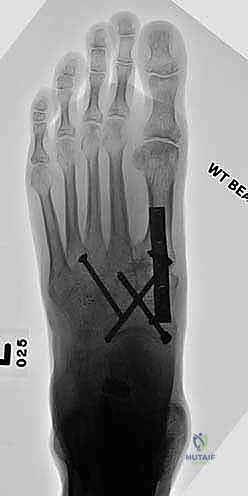

6. التثبيت الصلب (Rigid Fixation)

لضمان التحام العظام لتصبح عظمة واحدة صلبة، يجب تثبيتها بقوة هائلة حتى لا تتحرك أثناء فترة الشفاء. يتم استخدام مسامير معدنية متطورة (Screws)، أو شرائح معدنية خاصة (Plates)، أو دبابيس طبية متخصصة (Staples) مصنوعة من التيتانيوم الآمن على الجسم.

7. الإغلاق والضماد

بعد التأكد التام من وضع العظام وثباتها باستخدام جهاز الأشعة السينية داخل غرفة العمليات (C-Arm)، يتم إغلاق الشقوق الج